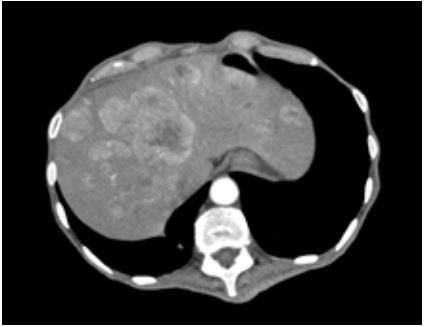

Paciente masculino, 64 anos, veio encaminhado para avaliação de quadro de fraqueza, perda de peso (23Kgs nos últimos seis meses) e evacuações diarreicas cerca de 20x ao dia, sem muco, sangue ou pus. Em uso domiciliar de glicazida 60mg ao dia devido a diagnóstico recente de diabetes. Ao exame físico emagrecido, com índice de massa corpórea de 15 Kg/m² , com placas orais sugestivas de monilíase, erosões crostosas e placas amarronzadas no dorso e membros, com fígado endurecido, palpável a 4 cm do rebordo costal direito. Exames laboratoriais evidenciaram anemia normocítica e normocromica, discreta plaquetose, hipoalbuminemia, com sorologias para hepatites virais e HIV negativas. Exame de fezes com gap osmolar fecal de 5,02 Osm / kg H2O, ausência de hemácias, leucócitos, leveduras, ácidos graxos, helmintos ou protozoários. Tomografia contrastada de abdome mostrou lesão sólida com captação de contraste de 2,4cm em corpo / cauda de pâncreas e múltiplas lesões nodulares hepáticas, estas evidenciadas na figura a seguir:

Com relação a este caso é correto afirmar: